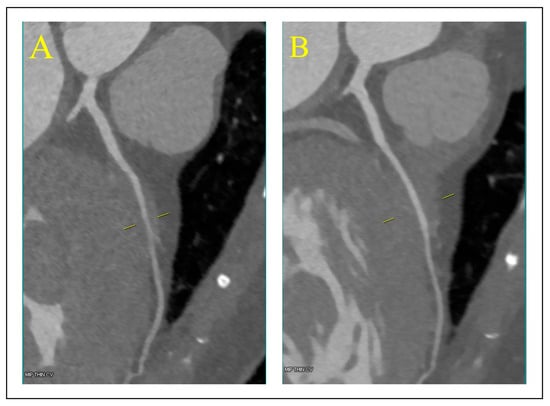

3.4. Cardiac Magnetic Resonance